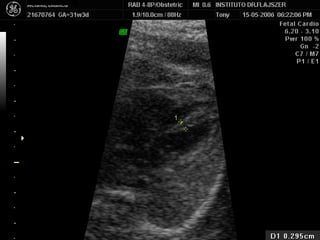

Evaluación del corazón fetal en la ecografía obstétrica Modo B ¿CUANDO? Segundo y tercer trimestres ¿Como? De mayor a menor

1) LONGITUDINAL / CEFALICA / DORSO IZQ

Apex y estómago: ¿Cerca o lejos del transductor? Lejos Long/Cef/D.izq